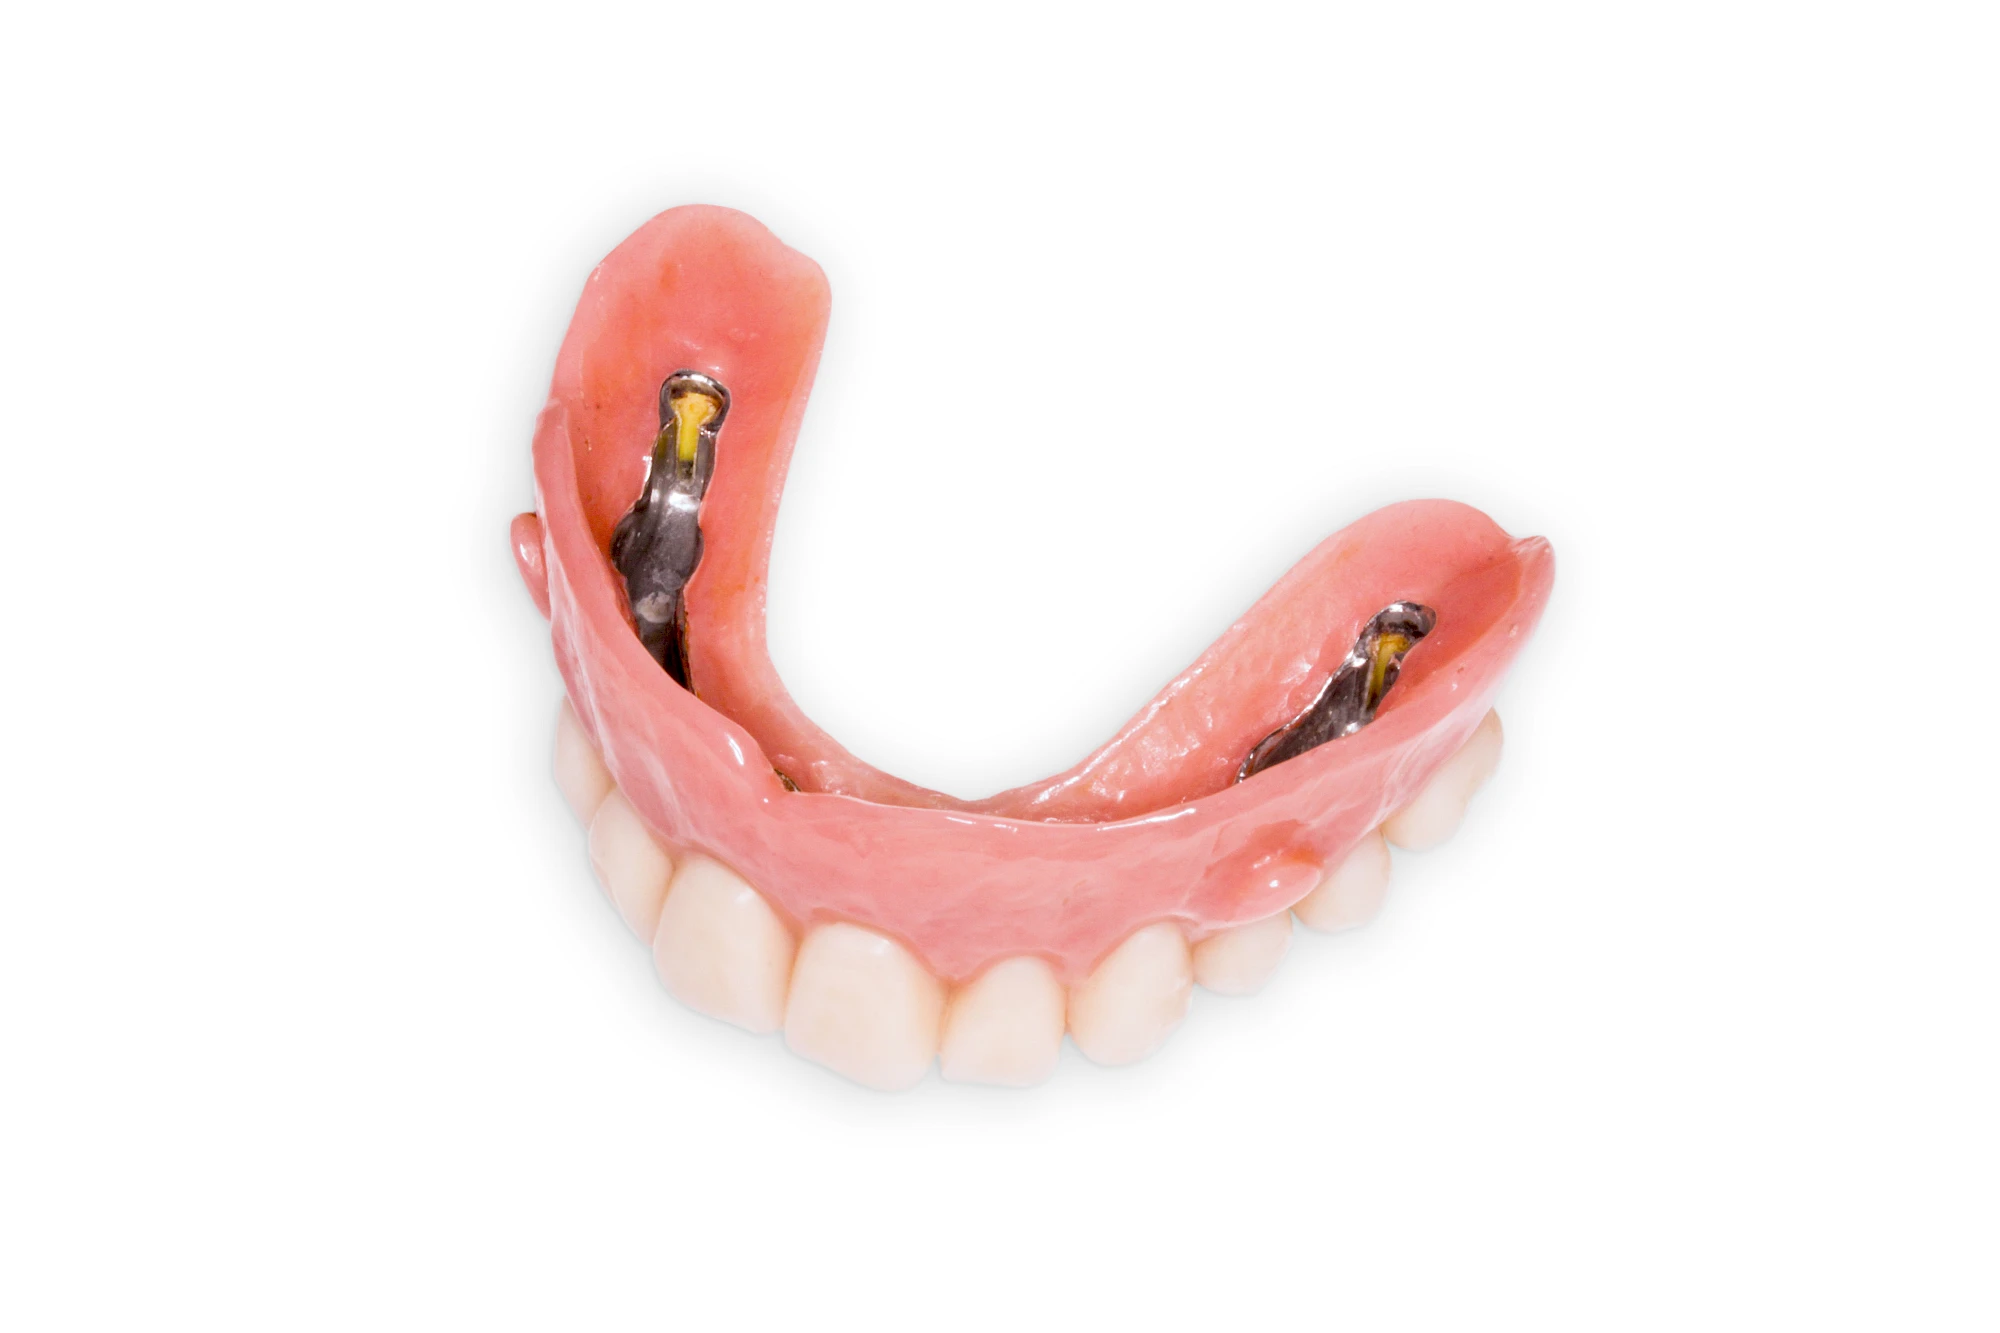

Implantate: Prothesen

Bei herausnehmbaren Prothesen werden Implantate eingesetzt, um den Halt und den Tragekomfort der Prothesen zu verbessern. Dazu kommen verschiedene Verbindungselemente zum Einsatz:

- Teleskope

- Kugelköpfe

- Tellerförmige Lokatoren

- Stege

- Magnete (selten)

Neben rein implantat-getragenen zahnärztlichen Versorgungen werden bei herausnehmbaren Prothesen Implantate auch in Sinne einer "strategischen Pfeilervermehrung" ergänzend zu eigenen Zähnen zur Verankerung eines Zahnersatzes genutzt.

Varianten zur Verankerung von abnehmbarem Zahnersatz auf Implantaten